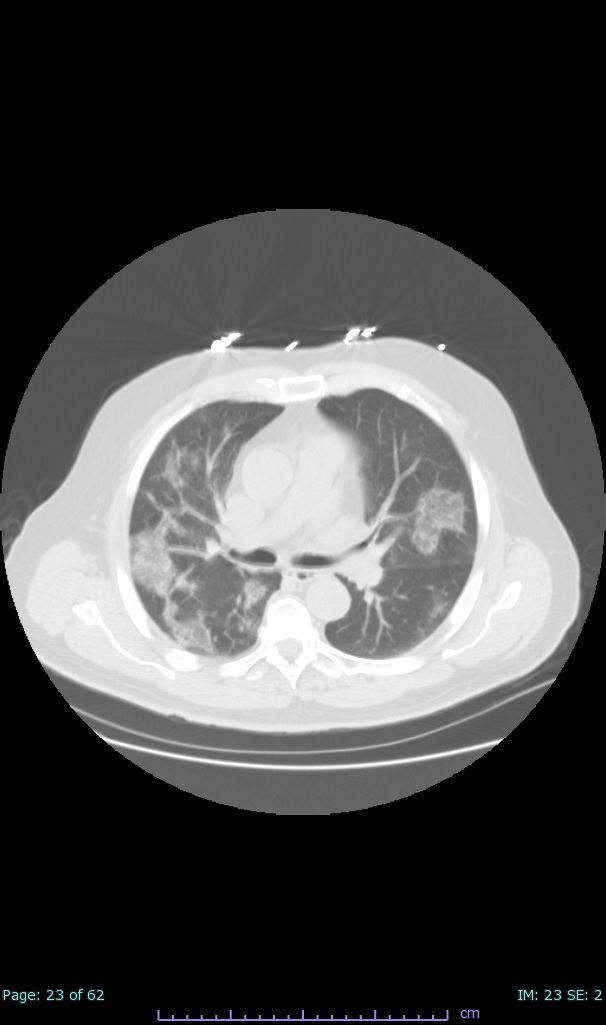

- 100% subpleural involvement, 33% + centrolobular involvement

- 40% even apical/basilar, 27% basilar dom, 5% mid dom. 1/17